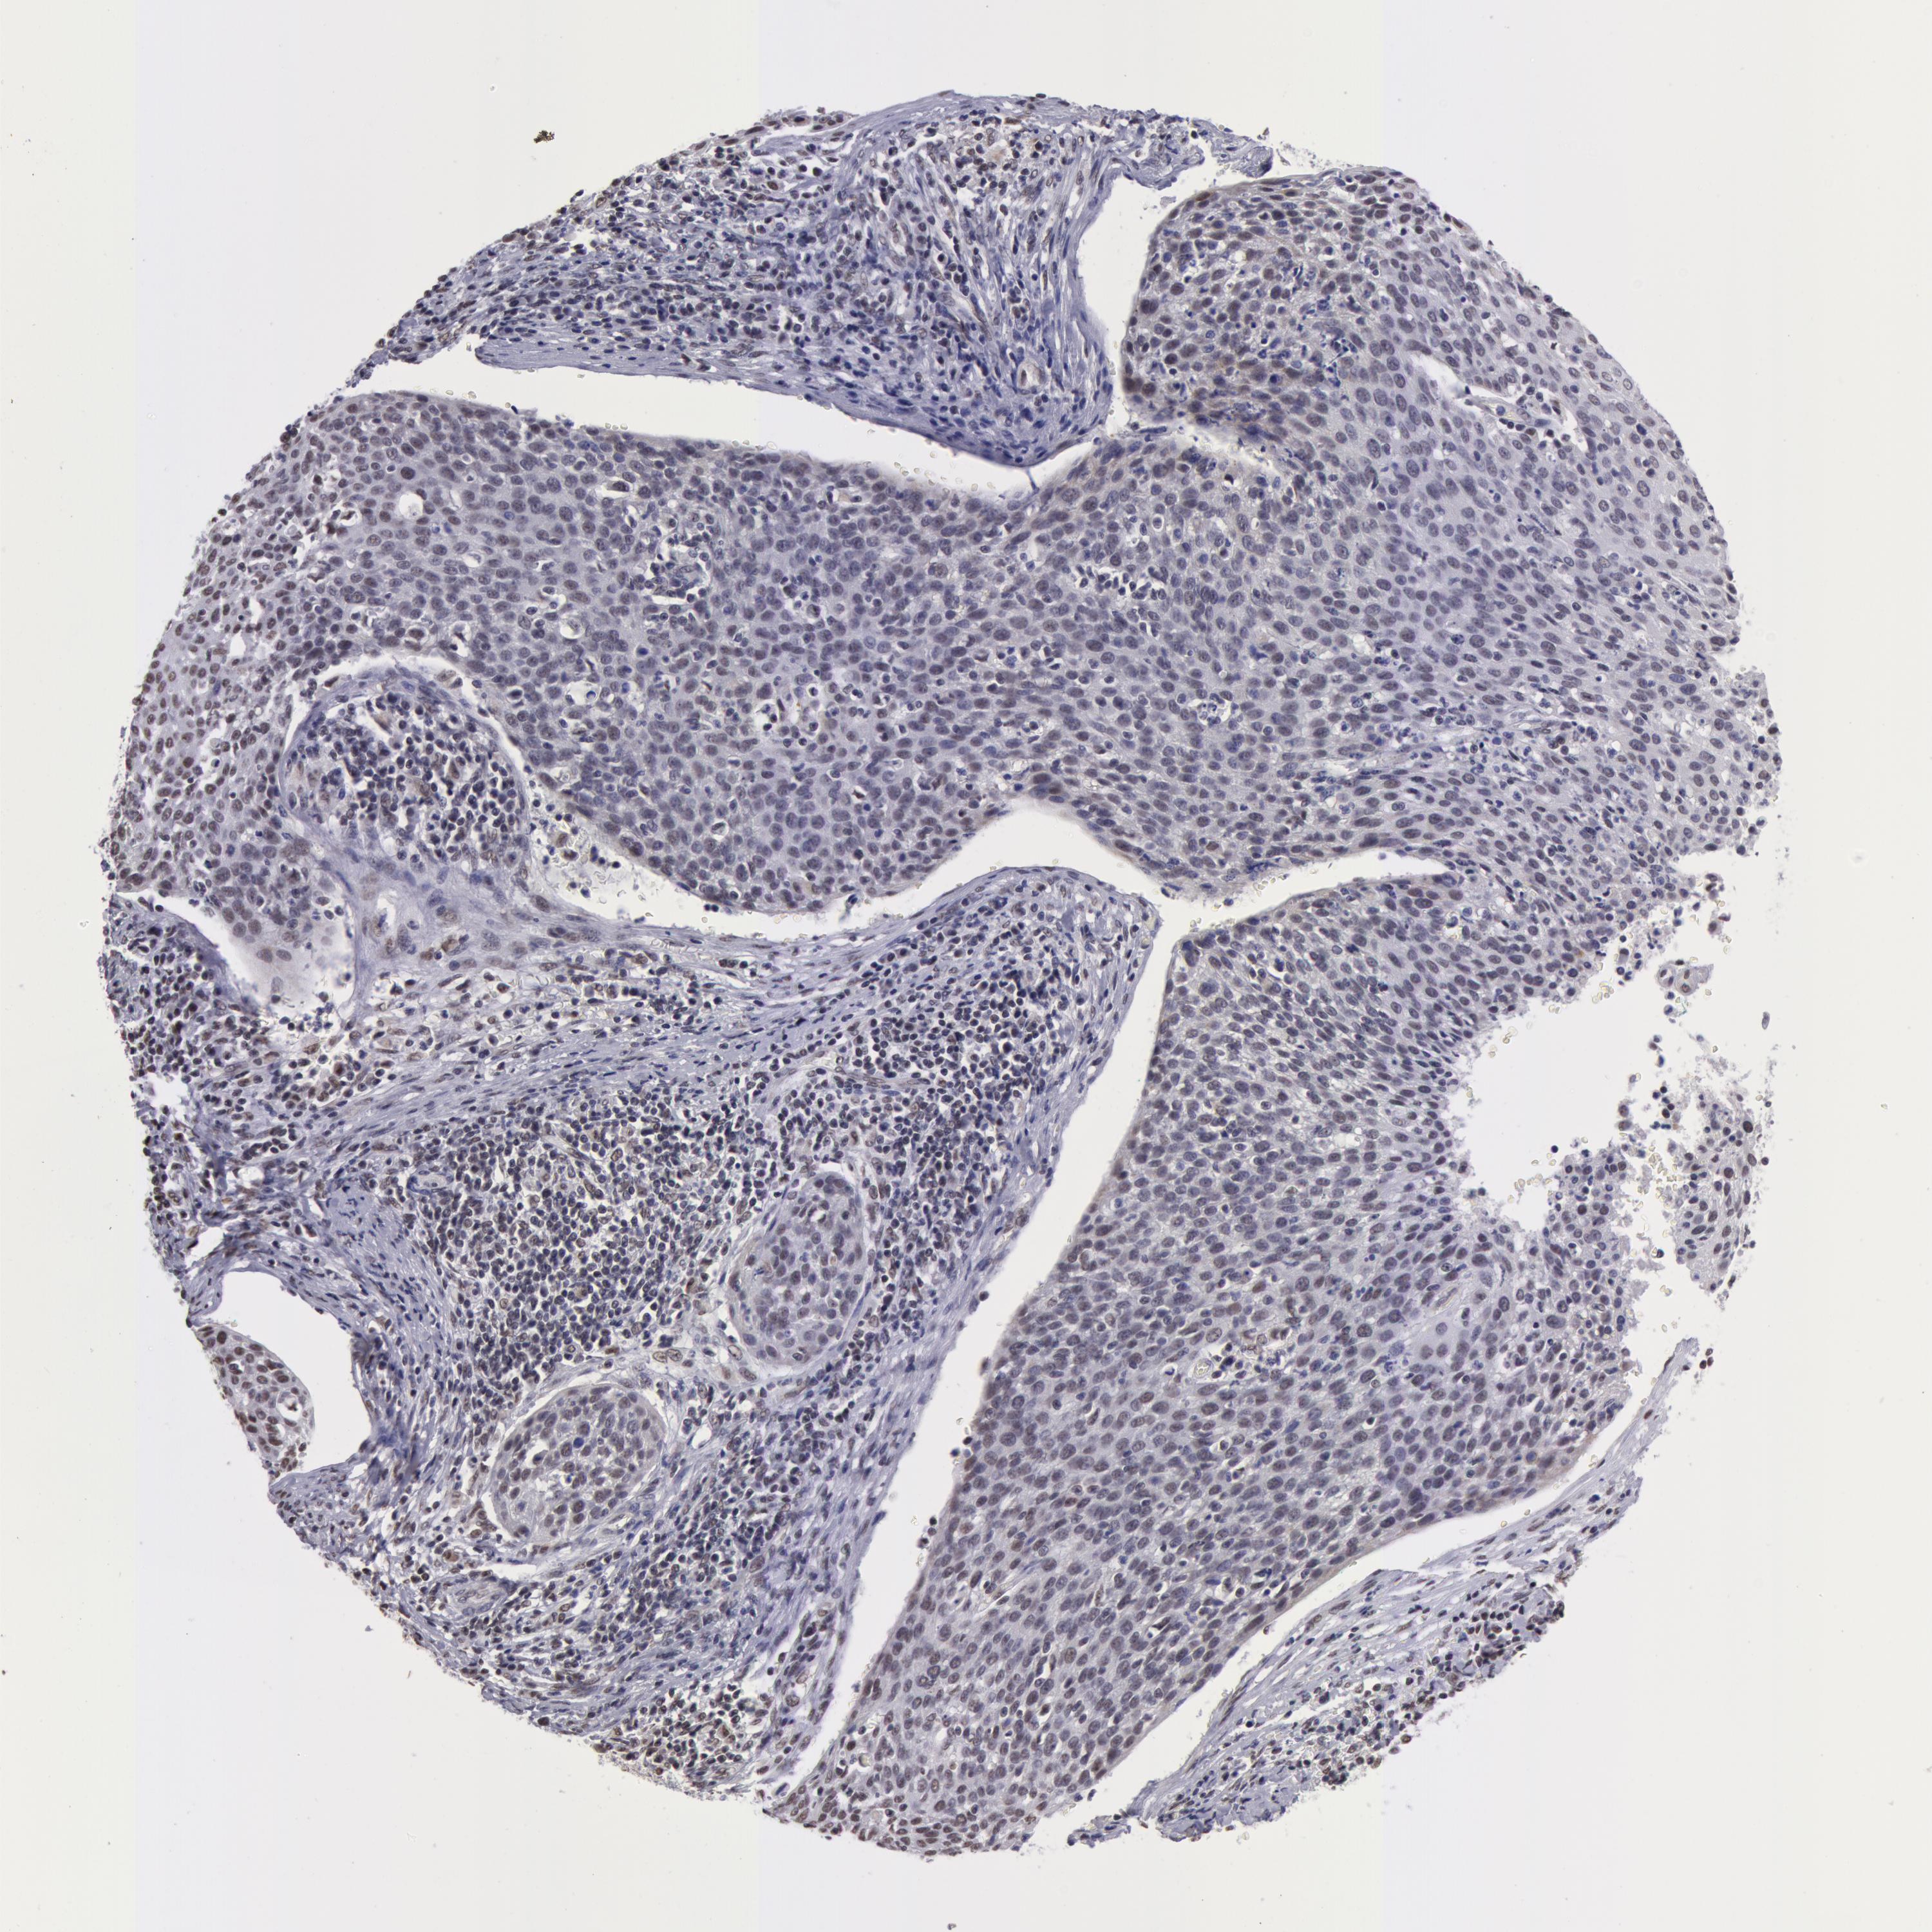

CERVICAL CANCER - Protein expressioni

A mouse-over function shows sample information and annotation data. Click on an image to view it in a full screen mode. Samples can be filtered based on level of antibody staining by selecting one or several of the following categories: high, medium, low and not detected. The assay and annotation is described here.

Note that samples used for immunohistochemistry by the Human Protein Atlas do not correspond to samples in the TCGA dataset.

Antibody stainingi

Antibody staining in the annotated cell types in the current human tissue is reported as not detected, low, medium, or high, based on conventional immunohistochemistry profiling in selected tissues. This score is based on the combination of the staining intensity and fraction of stained cells.

Each image is clickable and will lead to virtual microscopy that enables deeper exploration of all samples and also displays staining intensity scores, fraction scores and subcellular localization as well as patient and tissue information for each sample.

Antibody HPA001460

Staining

High

Medium

Low

Not detected

Intensity

Strong

Moderate

Weak

Negative

Quantity

>75%

75%-25%

<25%

None

Location

Nuclear

Cytoplasmic/membranous

Cytoplasmic/membranous,nuclear

Adenocarcinoma, NOS

Squamous cell carcinoma, NOS